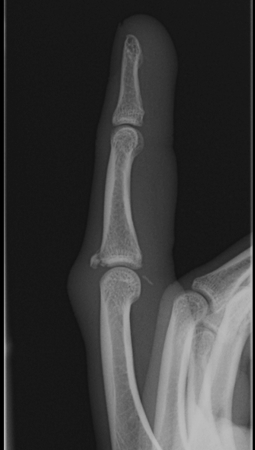

PIPJ Dislocations

Dorsal dislocations PIPJ

Most common joint injury of the hand

- hinge joint permitting 110o ROM

- volar plate fails distally

- collateral ligaments may be intact

- may be a fracture